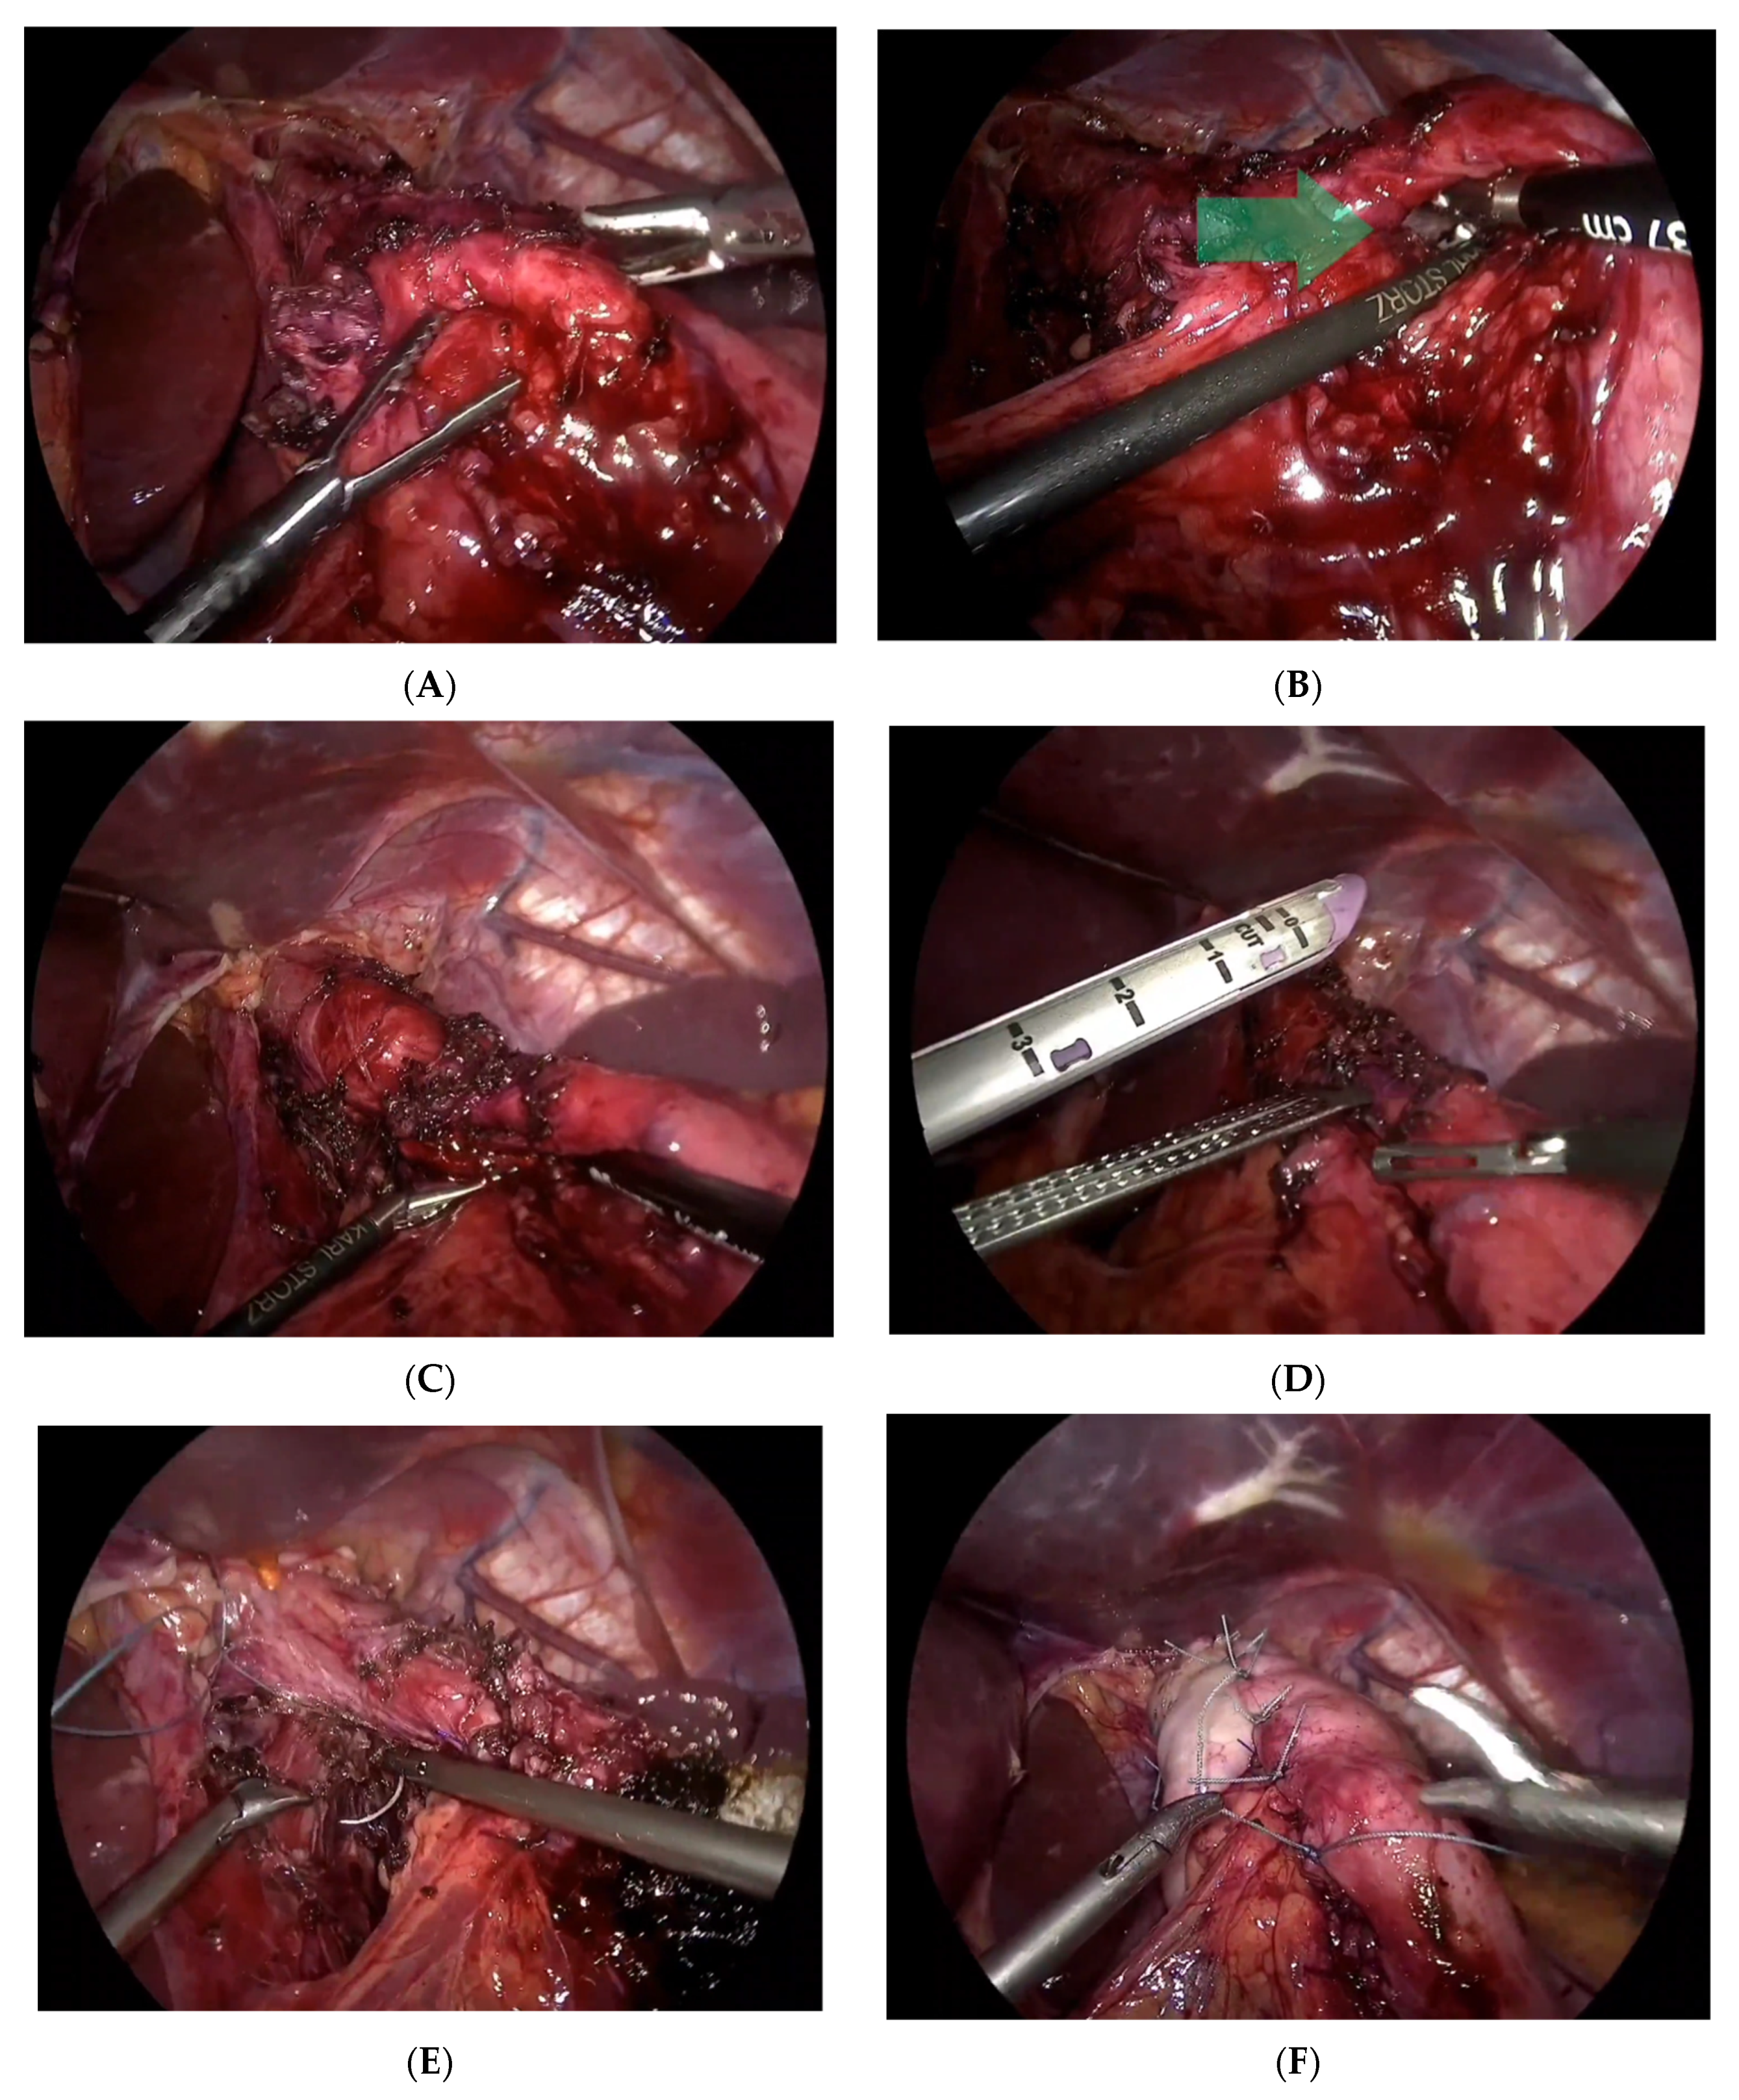

Under general anesthesia in the supine open-leg position, cleaning and toweling were performed. Three trocars were inserted at 11, 12, and 5 mm after insufflation of the abdomen by CO2 up to 14 mmHg pressure. A 2 mm liver retractor was used as it was a huge fatty liver. On examination, there was a gastro-gastric fistula, in addition to a hiatal hernia, which was easily reduced from the mediastinum after adhesiolysis (Figure 2). And there was a complete exposure of the esophageal hiatus.

The gastrohepatic ligament was opened over the caudad lobe of the liver using the ligasure device, and the hepatic branch of the vagus nerve was identified and carefully preserved. The peritoneal incisions were extended over the left and right crus, and the mediastinum was entered. The esophagus was circumferentially mobilized, and all vessels encountered were controlled by the ligasure. The short gastric vessels were divided to the level of the left crus to ensure that the entire posterior aspect of the upper fundus of the stomach was completely mobilized. Upon careful dissection and release of the old endoscopic Nissen stitches, we identified a gastro-gastric fistula. The fistula was confirmed by the passage of a nasogastric tube of large caliber. Dissection and excision of the fistula tract were performed using GIA purple. A stabler of size 60 mm twice, followed by oversuturing the stabler lines by PDS 3-0.

We confirmed that there are no gastric injuries. Proceeding to the closure of the diaphragmatic defect, we closed it posteriorly using Ethibond 2-0. Then, the fundoplication was completed using interrupted 2-0 Ethibond sutures (crurogastric, cranoesophageal, and gastrogastric) and modified toupet stitches to fix the wrap and avoid intrathoracic slippage. The suture line was oriented at the 10 to 11 o’clock position, and the superior and inferior sutures were anchored to the wall of the esophagus. The medial stitch was placed between the walls of the fundus of the stomach. The calibration tube was easily removed and reinserted twice to make sure the passage was patent and there was no twist or narrowing in the stomach or evidence of tension.

Figure 2. Laparoscopic procedures in the management of endoscopic fundoplication complications (A) exploring the previous endoscopic fundoplication; (B) a deep, full-thickness endoscopic stitch and fistula (the fistula is pointed by the green arrow); (C) using a nasogastric tube to confirm the presence of a fistula; (D) cutting the fistula using GIA; (E) repair of the hiatus; (F) Nissen fundoplication ended by Rossetti stitch.